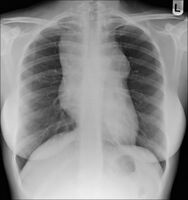

Hodgkin lymphoma (gross pathology)

Hodgkin lymphoma

Hodgkin lymphoma- hilum overlay sign

After Hodgkin lymphoma is diagnosed, a person will be staged: that is, they will undergo a series of tests and procedures that will determine what areas of the body are affected. These procedures may include documentation of their histology, a physical examination, blood tests, chest X-ray radiographs, computed tomography (CT)/Positron emission tomography (PET)/magnetic resonance imaging (MRI) scans of the chest, abdomen and pelvis, and usually a bone marrow biopsy. Positron emission tomography (PET) scan is now used instead of the gallium scan for staging. On the PET scan, sites involved with lymphoma light up very brightly enabling accurate and reproducible imaging.[29] In the past, a lymphangiogram or surgical laparotomy (which involves opening the abdominal cavity and visually inspecting for tumors) were performed. Lymphangiograms or laparotomies are very rarely performed, having been supplanted by improvements in imaging with the CT scan and PET scan.